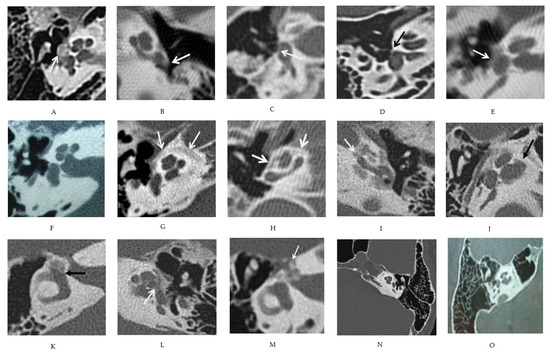

3.1. Description of Various CT Features